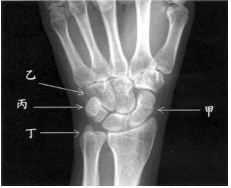

53 如右圖所示,何部位發生骨折後比較容易產生骨壞死?

(A) 甲 (B) 乙 (C) 丙 (D) 丁